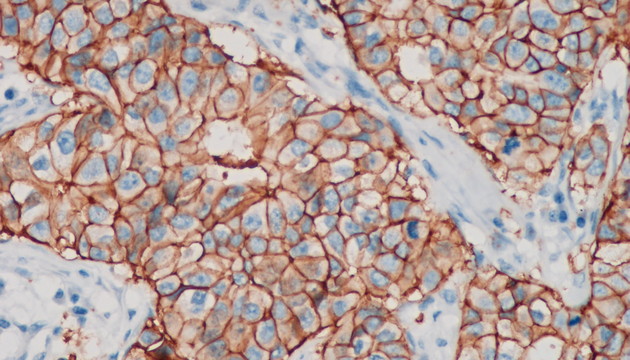

依據癌細胞在分子表達層面和細胞組織層面的變化,運用各類顯微成像技術對癌細胞進行篩選與識別,如①病理切片②免疫組化(IHC)③原位熒光雜交(FISH)④循環腫瘤檢測(CTC)⑤腫瘤細胞培養研究

癌癥研究中的成像有明場和熒光兩類,明場設備要求低,但病理切片全片判讀工作量大,效率低,使用切片掃描系統通過電動掃描和拼接軟件,實現高效全局成像與局部放大,可提升診斷精度與效率;多色熒光成像高靈敏度、高特異性,但信號弱,需優化激發光、濾光片、成像設備及圖像處理,以獲取清晰多通道信號;對于細胞培養,還有如何長時間成像監測,同時減少污染、不影響細胞生長的困難

(1)全能型設備:明美數字切片掃描系統MDS4+MSX2/MS60,融合切片掃描功能與研究級熒光顯微鏡,適用于病理切片、CTC、FISH、IHC等多種檢測。 (2)FISH、CTC、IHC專用:MF43-N/MF53-N+MS23/MSX11,搭配FISH軟件,支持多色熒光通道,高靈敏度成像,智能優化圖像。 (3)癌細胞培養觀測:活細胞成像儀MCS11/MCS21/MCS22+電腦,培養箱內使用,無線連接遠程管理,減少污染風險,集成多種成像模式,滿足多樣細胞培養觀測需求。